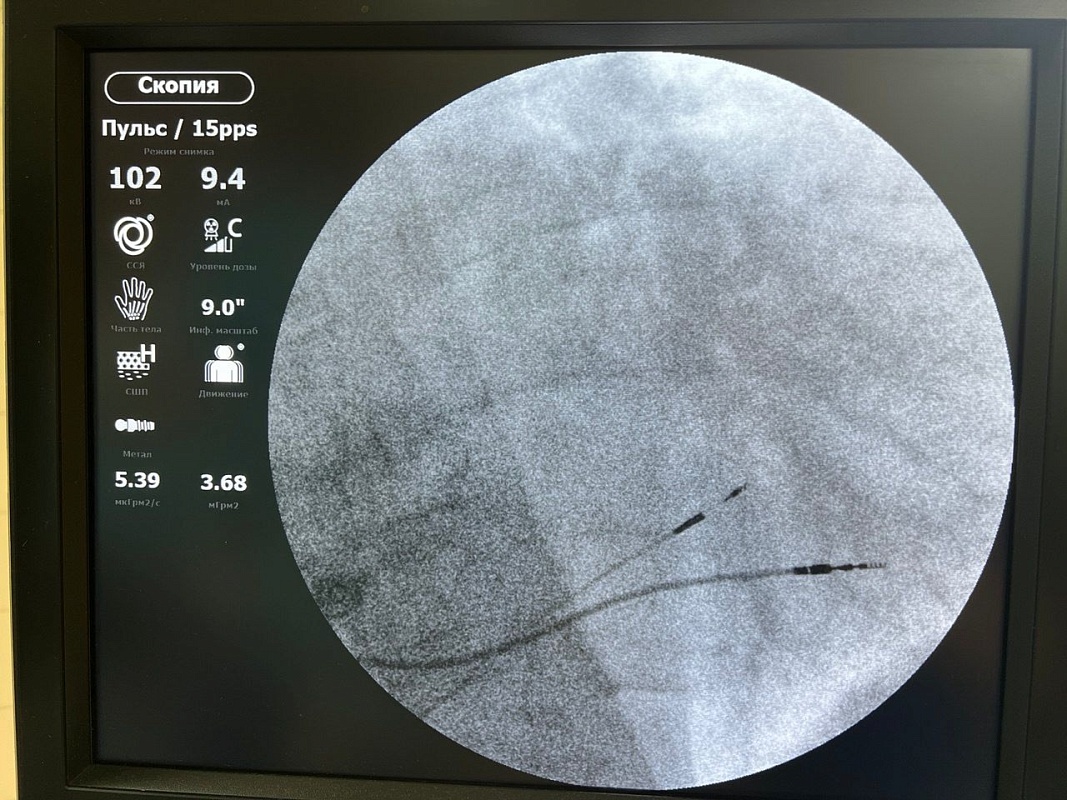

В Рязани впервые поставили кардиостимулятор с имплантацией электродов напрямую

В Рязани начали использовать новый способ установки электрокардиостимуляторов. О современной методике рассказали в региональном минздраве.

"Впервые специалисты установили электрод в межжелудочковую перегородку сердца для стимуляции проводящей системы напрямую", - пояснили представители ведомства.

Первым пациентом, которого прооперировали по такой методике, стал 78-летний рязанец. Пульс у него падал до 40 ударов в минуту, были проблемы с сердцем. Стандартный способ установки стимулятора ему не подходил. Теперь же мужчина заканчивает реабилитацию, скоро отправится домой. Пульс удалось нормализовать, и сердце работает уже заметно лучше.

Иллюстрации:  минздрав Рязанской области